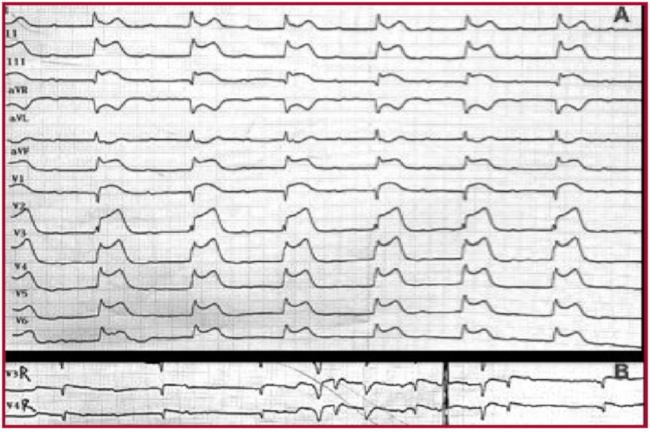

Presentamos el caso de un hombre de 68 años con antecedentes de tabaquismo y diabetes mellitus tipo 2, sin otro antecedente personal o familiar de enfermedades, quien fue atendido en el servicio de urgencias por un episodio de una hora con dolor torácico, disnea y diaforesis. Al examinarlo, presentaba frecuencia cardíaca de 40 latidos por minuto (lpm) y presión arterial media de 70 mmHg. Se encontraba nervioso; la auscultación reveló bradicardia con ruidos respiratorios normales, el resto del examen fue normal. El electrocardiograma (ECG) inicial mostró una lesión subepicárdica en la pared anterior e inferior con compromiso del ventrículo derecho (VD), y un bloqueo atrioventricular (AV) de 3.o grado (Figura 1). El paciente recibió tratamiento con aspirina 300 mg, clopidogrel 300 mg, enoxaparina 30 mg y un único bolo de tenecteplasa ajustado por peso dentro de los primeros 15 minutos del diagnóstico de infarto de miocardio. Sin embargo, el paciente desarrolló shock cardiogénico y el ECG no mostró ningún criterio de reperfusión 60 minutos después de la trombólisis. En ese momento, los indicadores de riesgo del IMEST fueron GRACE 181 puntos (40% de probabilidad de muerte desde el ingreso hasta los 6 meses) y TIMI 9 puntos (35,9% de riesgo de mortalidad por cualquier causa a los 30 días). El paciente fue entonces trasladado a la unidad de cateterismo cardíaco para someterlo a una angioplastía de rescate con soporte de norepinefrina y dobutamina. En primer lugar, se colocó un electrodo de marcapasos en el ventrículo derecho a través de la vena femoral y se programó en modo VVI con una frecuencia de 70 lpm; la angiografía coronaria mostró trombo intraluminal y un 70% de estenosis en el segmento proximal de la arteria coronaria derecha (CD) con flujo TIMI 2. Simultáneamente, la arteria descendente anterior (DA) izquierda mostró trombo intraluminal y estenosis del 80% en el segmento medio con flujo TIMI 2. Se implantó un stent liberador de everolimus (Xience-Alpine: 4,0 × 28 mm) en la CD y dos stents liberadores de everolimus (Xience-Alpine: 3,5 × 18 mm y 4,0 × 18 mm) se implantaron en la DA con superposición de stents. La última angiografía mostró las dos arterias con flujo TIMI grado 3 (Figura 2). Posteriormente, el ECG mostró un ritmo sinusal normal y marcadores de reperfusión con normalización del segmento ST de las inversiones del segmento ST y de la onda T en las derivaciones afectadas. El ecocardiograma reveló discinesia del VD con un cambio del área fraccional del 22% y fracción de eyección del ventrículo izquierdo del 46%. El soporte inotrópico y los vasopresores fueron suspendidos en menos de 48 horas. Tras la rehabilitación cardíaca en el hospital, el paciente finalmente fue dado de alta 8 días más tarde con seguimiento médico en los consultorios externos de cardiología. En la última consulta cardiológica, seis meses después del evento, el paciente manifiesta no tener síntomas cardiovasculares en sus actividades diarias ni tampoco durante los ejercicios aeróbicos, por lo que su afección tiene una clase funcional I según la New York Heart Association.